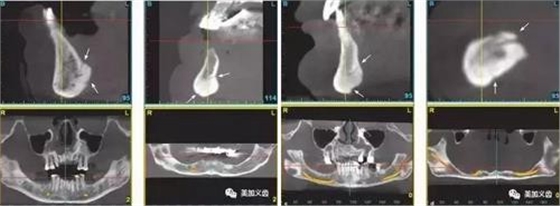

5、術(shù)前一定要拍CT,研究植入位點解剖結(jié)構(gòu)。

1、舌下動脈分支可通過副舌孔進入前磨牙或前牙區(qū)下頜骨(中線處較多見)。

4、無牙頜患者牙槽骨嚴重吸收者,舌頦動脈離牙槽嵴頂近,種植體植入易傷及舌頦動脈。